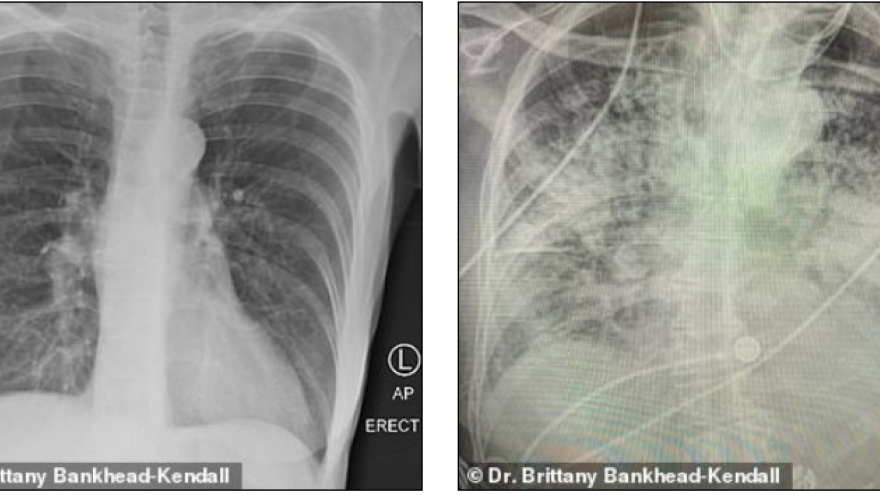

VOV.VN - Giám đốc Trung tâm Kiểm soát và phòng ngừa dịch bệnh Mỹ (CDC) hôm 22/7 khẳng định biến thể Delta của Covid-19 là một trong các virus gây bệnh hô hấp có sức lây nhiễm khủng khiếp nhất mà các nhà khoa học từng được chứng kiến.